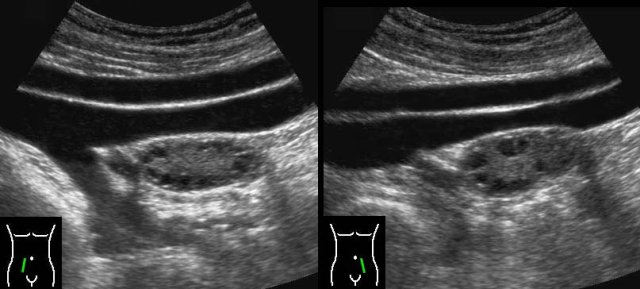

PID case 4

These images are of a very ill, painful young woman with generalized peritonitis and a CRP of 250, clinically suspect for perforated appendicitis.

US showed aperistaltic small bowel (b.).

The appendix

was not visualized.

TVUS showed a normal uterus and normal ovaries (arrowheads), which were surrounded by hyperechoic tissue (*).

CT confirmed the paralytic ileus and showed a normal appendix (arrow).

PCR was positive for gonorrhoea.